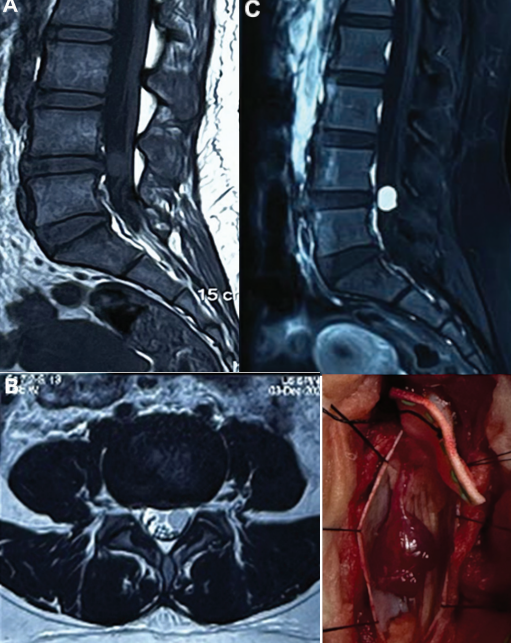

👩💼25F with 1-year history of low back pain and progressive left-sided radiculopathy, no motor deficit, normal reflexes. Symptoms worsening despite conservative management. 🩺What’s your differential?